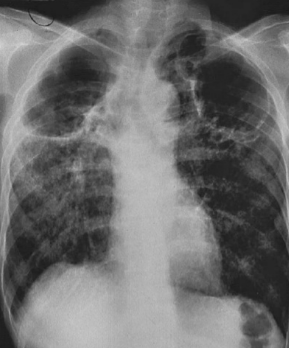

EM UM PACIENTE COM TUBERCULOSE PULMONAR, O QUE PODEMOS EVIDENCIAR EM UM RAIO-X DE PULMÃO?

- CAVITAÇÕES EM ÁPICE COM PRESENÇA DE AR

- CALCIFICAÇÕES

- DERRAME PLEURAL

- INFILTRADOS podem estar presentes